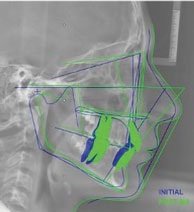

Figs. 3a-g: Initial records.

Fig. 3a

Fig. 3b

Fig. 3c

Fig. 3d

Fig. 3e

Fig. 3f

Fig. 3g

Table 1: Initial key cephalometric values.